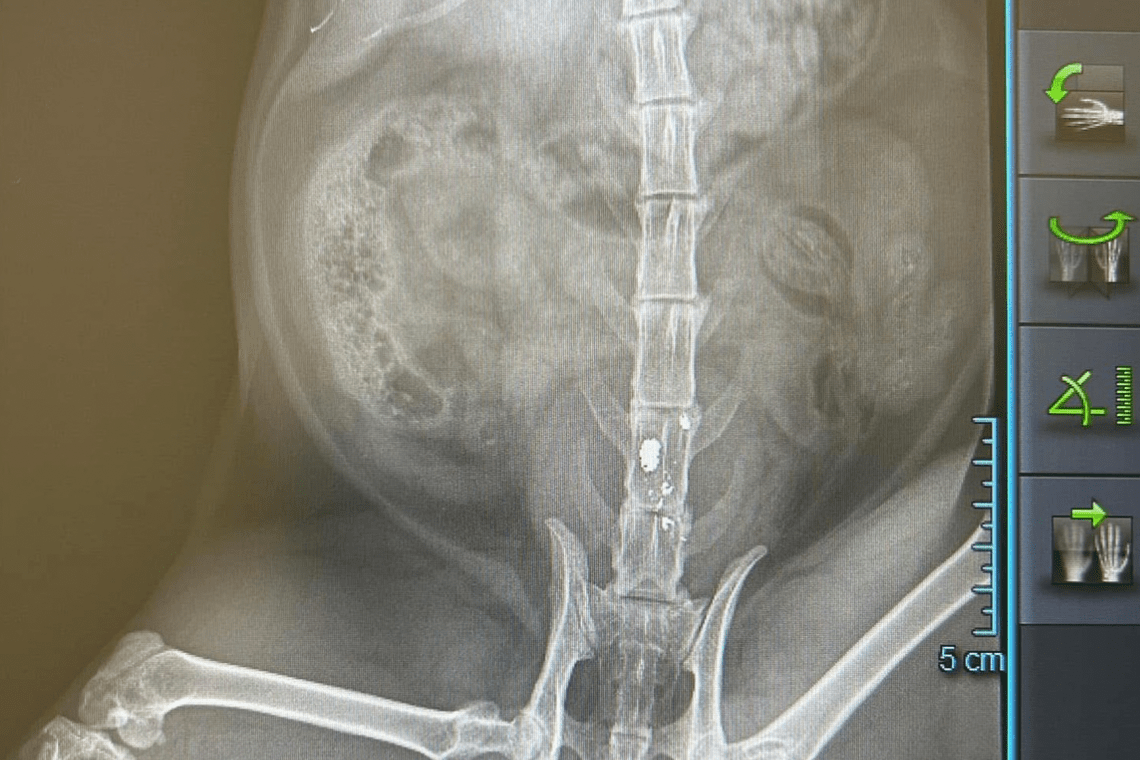

Den berørte beboer fortæller, at deres kæledyr, som normalt er en aktiv og dygtig jæger, pludselig blev fundet i en tilstand af nød. Dyrlægeundersøgelser afslørede, at kæledyret var blevet ramt af et hagl, der havde forårsaget alvorlig skade på rygraden og ført til lammelse. Hændelsen er blevet politianmeldt af den berørte beboer, i håb om at forhindre yderligere hændelser.